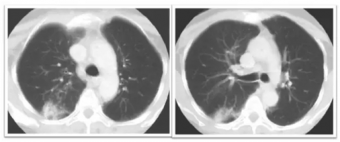

肺是放射敏感器官, 放射性肺炎 (Radiation Peumorutis RP)是指肺部一年內(nèi)接受過放射治療的患者,出現(xiàn)連續(xù)兩周以上的咳嗽、呼吸困難等肺部癥狀,同時(shí)肺部的影像學(xué)與照射野一致的片狀或條索狀陰影。RP是由炎性因子介...